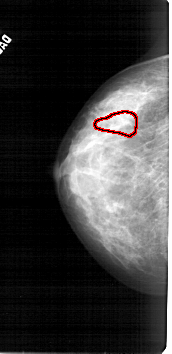

A_1783_1.RIGHT_CC

RIGHT_CC LINES 4861 PIXELS_PER_LINE 2401 BITS_PER_PIXEL 12 RESOLUTION 43.5 NON_OVERLAY

FILE: A_1783_1.LEFT_MLO.OVERLAY

TOTAL_ABNORMALITIES 1

ABNORMALITY 1

LESION_TYPE CALCIFICATION TYPE PLEOMORPHIC DISTRIBUTION SEGMENTAL

ASSESSMENT 4

SUBTLETY 2

PATHOLOGY BENIGN

TOTAL_OUTLINES 1

BOUNDARY